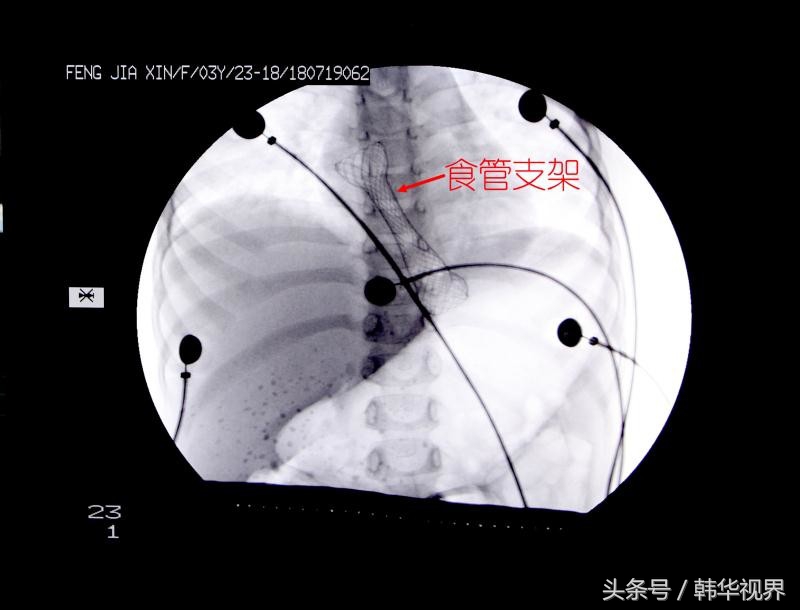

缪林主任告诉佳佳父母,一般人的食道有点损伤都能自愈。但是,佳佳的食道因为化学性烧伤比较严重,已经形成了瘢痕,粘膜没有了伸缩的能力,管腔明显缩小,所以无法进食。为了能够扩张食管,缪林特意为佳佳定制了一个特殊的食管支架。这个支架的长6cm,直径1.4cm,因为佳佳还是幼儿,且食道损伤的部位有限,所以定制了这个尺寸。支架是全覆膜的,主要考虑佳佳年龄小,身体还在生长发育,在其长大后,有可能会取出支架,所以采取全覆膜以方便后期取出。此外,缪林介绍,因为佳佳损伤主要在贲门附近,为了防止胃里的食物反流到食管内,在支架的下端特别做了防反流的瓣膜。

8月2日下午,缪林主任联合麻醉科、儿科等相关科室的医生,准备通过透视的方式进行手术,这样既安全又准确。考虑佳佳年龄太小无法配合,麻醉科施行了全麻。然后医生又为她在手术台上铺上了铅衣,尽量减少下半身的射线辐射。一切准备工作就绪,开始手术。缪林主任在透视射线的引导下,首先在食管内放置了一根导丝,以明确手术路径,然后又用超细胃镜对狭窄部位进行了扩张,最后成功将支架植入食管下端,手术顺利完成。佳佳妈妈一直焦虑的心终于得到安慰。记者了解到,接下来,佳佳经过2-3天的观察就能正常进食了。专家提醒,暑期是儿童意外事件高发的时期,家长一定要照看好孩子,并对孩子进行必要的安全教育,一旦发生意外伤害,及时到医院治疗。